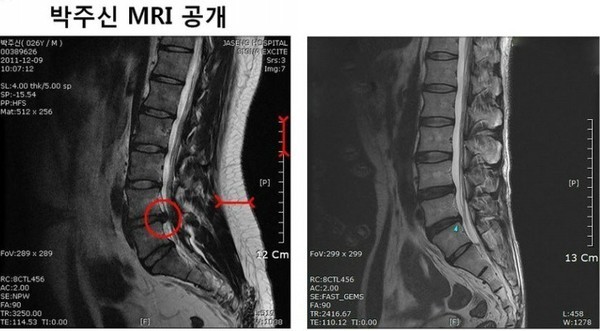

- ▲ 무소속 강용석 의원이 공개한 박원순 시장 아들 박주신의 MRI 사진(좌) 키 173cm 63kg 박주신과 같은 체형을 가진 허리디스크 환자의 MRI 비교. 전문의들은 좌측 사진에 대해 90kg 이상 고도비만 환자의 것이라는 분석을 내놨다. ⓒ강용석 의원실

전의총은 21일 ‘공개된 MRI 영상사진에 대한 소견’이라는 문건을 통해 “인터넷상에 공개된 자료를 살펴보면 MRI의 주인공은 30~40대 비만 환자로 날씬하고 마른 체형일 가능성은 거의 없고 20대일 가능성 또한 매우 희박하다”고 밝혔다.

병변 및 체형과 관련해 전의총이 구체적으로 내놓은 소견은 다음과 같다.

1. 병변

이 환자는 40세 이상일 가능성이 많다.

요추 4번과 5번간 척추체 사이에 완충 역할을 하는 연골인 디스크가 미만성 팽윤이 있는 상태에서 좌측으로 디스크가 돌출돼 좌측 신경관을 좁히고 있어 척추강협착증이 있음을 알 수 있다. 이와 함께 척추신경근을 압박하고 있어 이런 경우에 대부분 뚜렷한 증세 즉 심한 허리 통증과 다리 저림 등의 증세를 동반하며 일상생활에 지장을 준다.

요추의 추간판이나 후관절(facet joint)에 심하지는 않지만 퇴행성 변화가 존재하고 특히 후관절 부위에 골경화가 관찰되는 것으로 볼 때 환자는 20대 연령대라고는 생각하기 어려우며 적어도 30~40대 이상의 연령일 것으로 추정된다.

요추뿐 아니라 경추(목뼈)에도 C4-5, C5-6레벨에서 디스크 돌출이 관찰된다. 또한 정상적인 목뼈의 완만한 곡선이 사라져있고 경추의 척추제의 퇴행성변화가 뚜렷하게 관찰된다.

2. 체형

근육 내 지방량이 많다. 환자는 많은 양의 피하지방과 근육 내 지방의 변성을 보이고 있으므로 MRI 영상만으로 체형을 추정한다면 환자는 평소에 거의 운동을 하지 않는 중년으로 판단된다.

등과 배꼽 부위 등 전체적으로 피하지방층이 매우 두껍고, 특히 목 뒷부위의 피하지방층이 매우 두껍다. 허리 뿐 아니라 목 뒤부터 허리까지 전반적으로 두꺼운 지방층을 형성하고 있는 것이다. 영상을 기반으로 복부둘레를 추정하면 90cm (35인치) 이상이 될 것으로 추정된다.